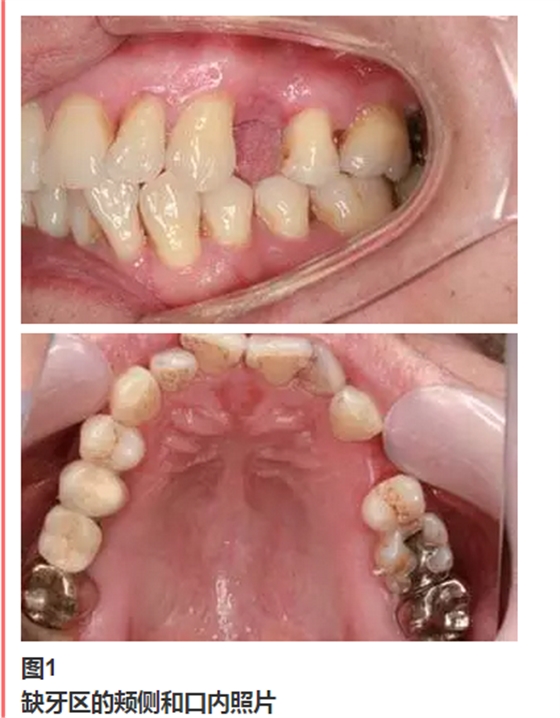

從圖1可以看出患者缺牙區(qū)的間隙充足,牙齦健康,頰側(cè)軟組織略有凹陷。